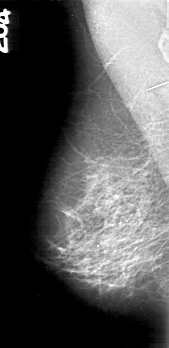

D_4162_1.RIGHT_MLO

LEFT_MLO LINES 5386 PIXELS_PER_LINE 2581 BITS_PER_PIXEL 12 RESOLUTION 43.5 OVERLAY

FILE: D_4162_1.LEFT_MLO.OVERLAY

TOTAL_ABNORMALITIES 1

ABNORMALITY 1

LESION_TYPE CALCIFICATION TYPE PLEOMORPHIC DISTRIBUTION CLUSTERED

ASSESSMENT 0

SUBTLETY 4

PATHOLOGY MALIGNANT

TOTAL_OUTLINES 1

BOUNDARY